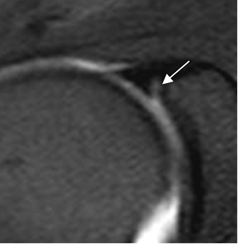

Fig 23. Ligamento glenohumeral superior normal.

A: RM axial en FFE y B: ArtroRM axial. Ligamento GHS normal.

Fig 24. Ligamento glenohumeral medio normal.

A: RM axial en FFE. Ligamento normal entre el labrum anterior y el tendón del subescapular.

B: ArtroRM axial y C: ArtroRM sagital en STIR. Ligamento GHM normal.

Fig 25. Ausencia del ligamento glenohumeral medio.

ArtroRM axial en STIR. No visualización del LGHM, por ausencia congénita. Tendón del subescapular normal. (Flecha).

Fig 26. Ligamento glenohumeral inferior normal.

A: ArtroRM axial y B: ArtroRM coronal. Banda anterior del ligamento GHI normal.

C: ArtroRM sagital. Banda anterior (Flecha delgada) y banda posterior (Flecha gruesa) normales.